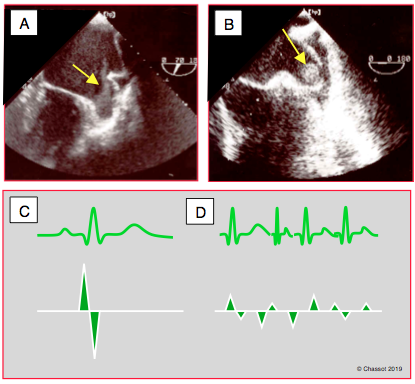

Figure 26.54 : Sténose mitrale (SM) lors de RAA. A : vue 4-cavités ; l’OG est gigantesque, le VG est petit ; la fusion commissurale retient les feuillets en diastole et l’ouverture (flèche) est minime. B : vue long-axe 120° montrant la déformation en canne de hockey (hockey stick) du feuillet antérieur en diastole. C : le corps du feuillet antérieur, resté souple mais retenu à la commissure, bombe dans l’OG en systole (doming) et dans le VG en diastole. D : bombement alterné du feuillet antérieur dans l'OG et dans le VG, avec une déformation typique (flèche) en diastole.

Figure 26.56 : Stase auriculaire gauche dans la sténose mitrale. A : contraste spontané dans l’appendice auriculaire gauche (état préthrombotique). B : présence d’un thrombus dans l’appendice auriculaire gauche. C: flux normal dans l'AAG; la Vmax est de 30-50 cm/s. D: flux dans l'AAG en cas de FA; la basse vélocité (≤ 20 cm/s) est un marqueur de risque pour la thrombose.